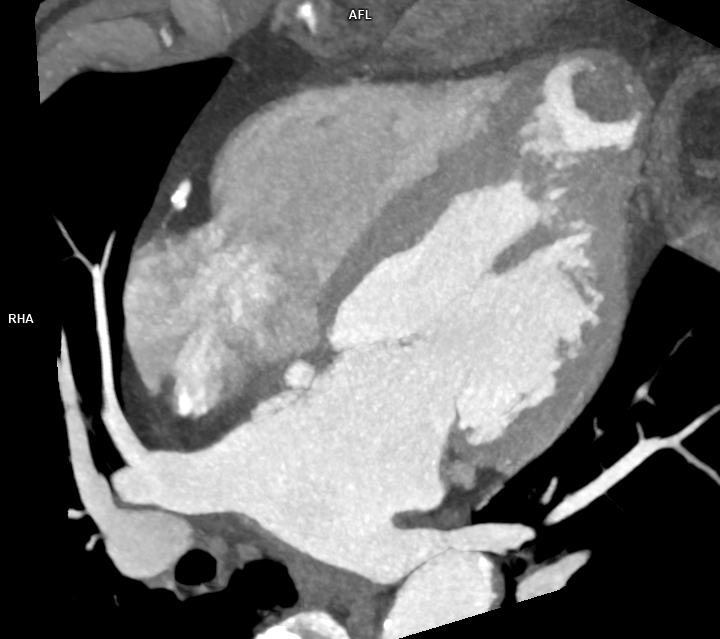

Figura 3: reconstrucție mutiplanară 4 camere din achiziție angioCT coronariană cu sincronizare ECG

Discuţie caz nr 120: Achiziția angioCT coronariană cu sincronizare ECG evidențiază ocluzie a arterei descendente anterioare în segmentul mediu cu hipokinezie severă / diskinezie a miocardului deservit și formarea unui anevrism antero-septal și apical ventricular stâng ce este locuit de un tromb.